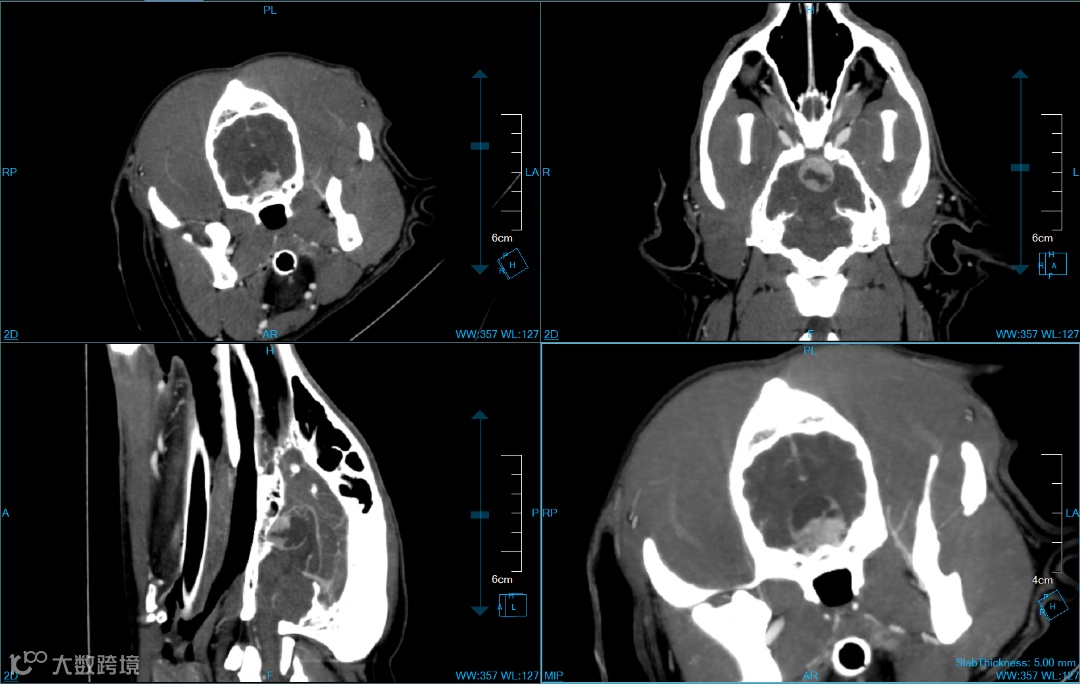

动物CT扫描包括横断面、冠状面和矢状面。仔细查看每个切面,以获取更全面的解剖信息。

多平面多方位观察垂体瘤形态

调整图像的窗宽和窗位,突出显示不同组织和病变的特征,最大程度展示病灶区域细节。

软组织窗、骨窗

注意不同结构、器官之间的位置,接触或推移关系等,有助于确定异常结构的原因。注意异常病变,如肿块、囊肿、结石的形态、大小、边界、密度和强化模式等特征。注意病变组织周围的反应,如炎症、水肿、增生或萎缩等,有助于评估病变的严重程度和影响范围。